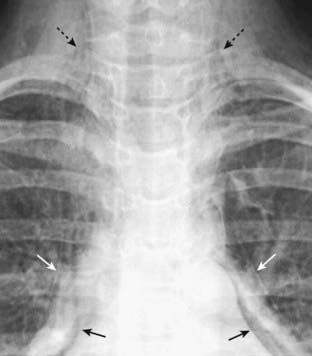

Figure 8-1 Visceral pleural line in a pneumothorax.

You must see the visceral pleural line to make the definitive diagnosis of a pneumothorax (solid white arrows). The visceral and parietal pleurae are normally not visible, both normally lying adjacent to the lateral chest wall. When air enters the pleural space, the visceral pleura retracts toward the hilum along with the collapsing lung and becomes visible as a very thin, white line with air outlining it on either side. Notice how the contour of the pneumothorax parallels the curvature of the adjacent chest wall.

Figure 8-3 Pneumothorax with pleural adhesions.

Lung markings may be visible on a conventional radiograph of the chest, distal to the visceral pleural line if pleural adhesions are present. In (A), a pneumothorax (solid white arrows) is prevented from collapsing the lung by pleural adhesions (solid black arrows). On a CT scan (B), the pleural adhesions (solid black arrows) are seen tethering the lung (solid white arrows) to the parietal pleura. Adhesions most frequently result from prior infection or blood in the pleural space.